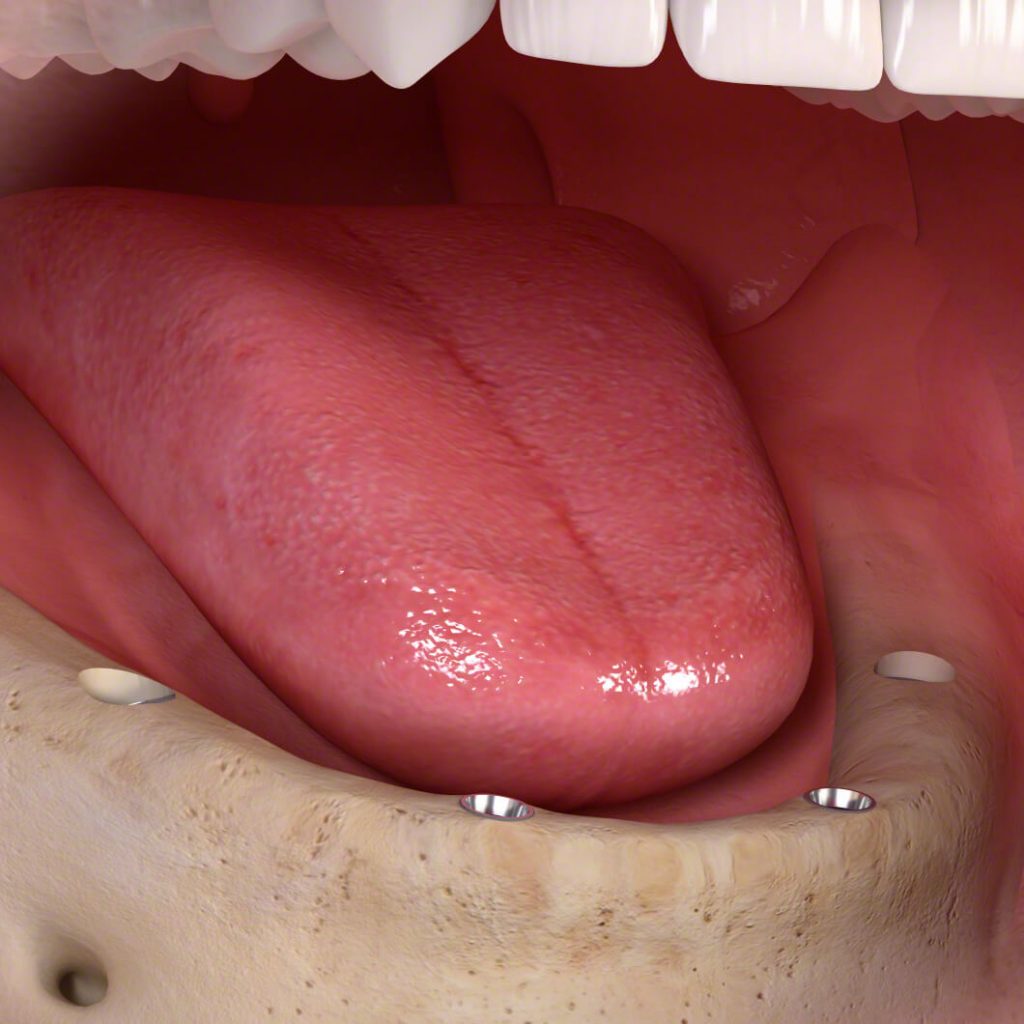

3.) Fog implantátum csavar beültetése A fogbeültetés helyi érzéstelenítésben történik, így a zsibbadáson kívül a páciens semmit sem érez. Az implantátum csavar helyét a csontban különböző gépi és kézi eszközökkel alakítjuk ki, majd ebbe a csontfészekbe csavarjuk a fogászati implantátumot. A fogimplantáció végén az implantátumot gyógyulási csavarral zárjuk le és az ínyen ejtett metszést varratokkal egyesítjük.

Ha szükséges csontot pótolni, bizonyos esetekben azt is ebben a fázisban végezzük el. Az esetek másik részében a csontpótlás egy külön alkalommal történik. Több fog implantátum egy idejű beültetésénél – mint például teljes fogsor implantátum beültetésénél – a SMART Guide cég navigált implantációs sebészeti rendszerét használjuk, ami fokozza az implantátum csavarok egymáshoz viszonyított térbeli helyzetének pontosságát.